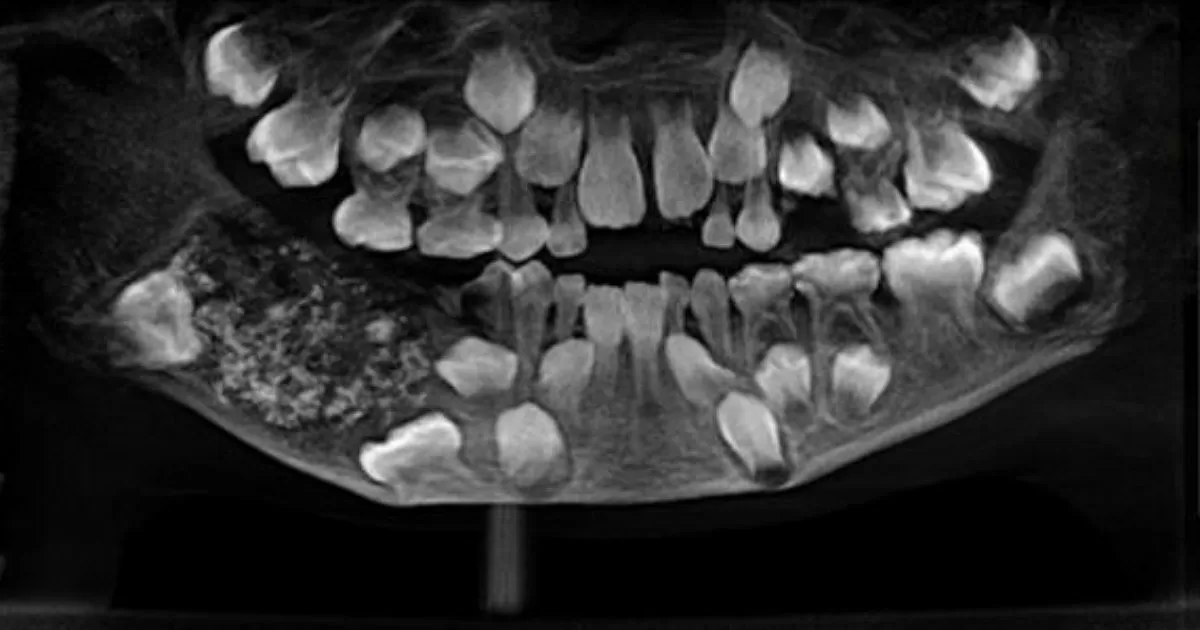

When doctors scanned and x-rayed his mouth, they found a sac embedded in his lower jaw filled with "abnormal teeth," Dr. Prathiba Ramani, the head of Oral and Maxillofacial Pathology at Saveetha Dental College and Hospital, told CNN.

After discovering the sac, two surgeons removed it from the boy's mouth. Then Ramani's team took four to five hours to empty the sac to confirm its contents and discovered the hundreds of teeth.

"There were a total of 526 teeth ranging from 0.1 millimeters (.004 inches) to 15 millimeters (0.6 inches). Even the smallest piece had a crown, root and enamel coat indicating it was a tooth," she said.